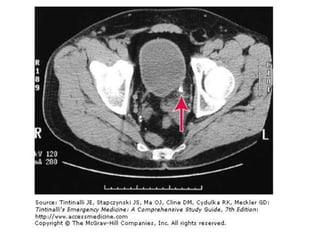

BT

• Non-kontrast helikal BT sensitif ve spesifiktir

Görüntüleme • • • • • Taşın varlığını kanıtlar Diğertanıları dışlatır komplikasyonIarı öngörür. Taşı lokalize eder Tedaviyi öngörür.

BT • Non-kontrast helikalBT sensitif ve spesifiktir